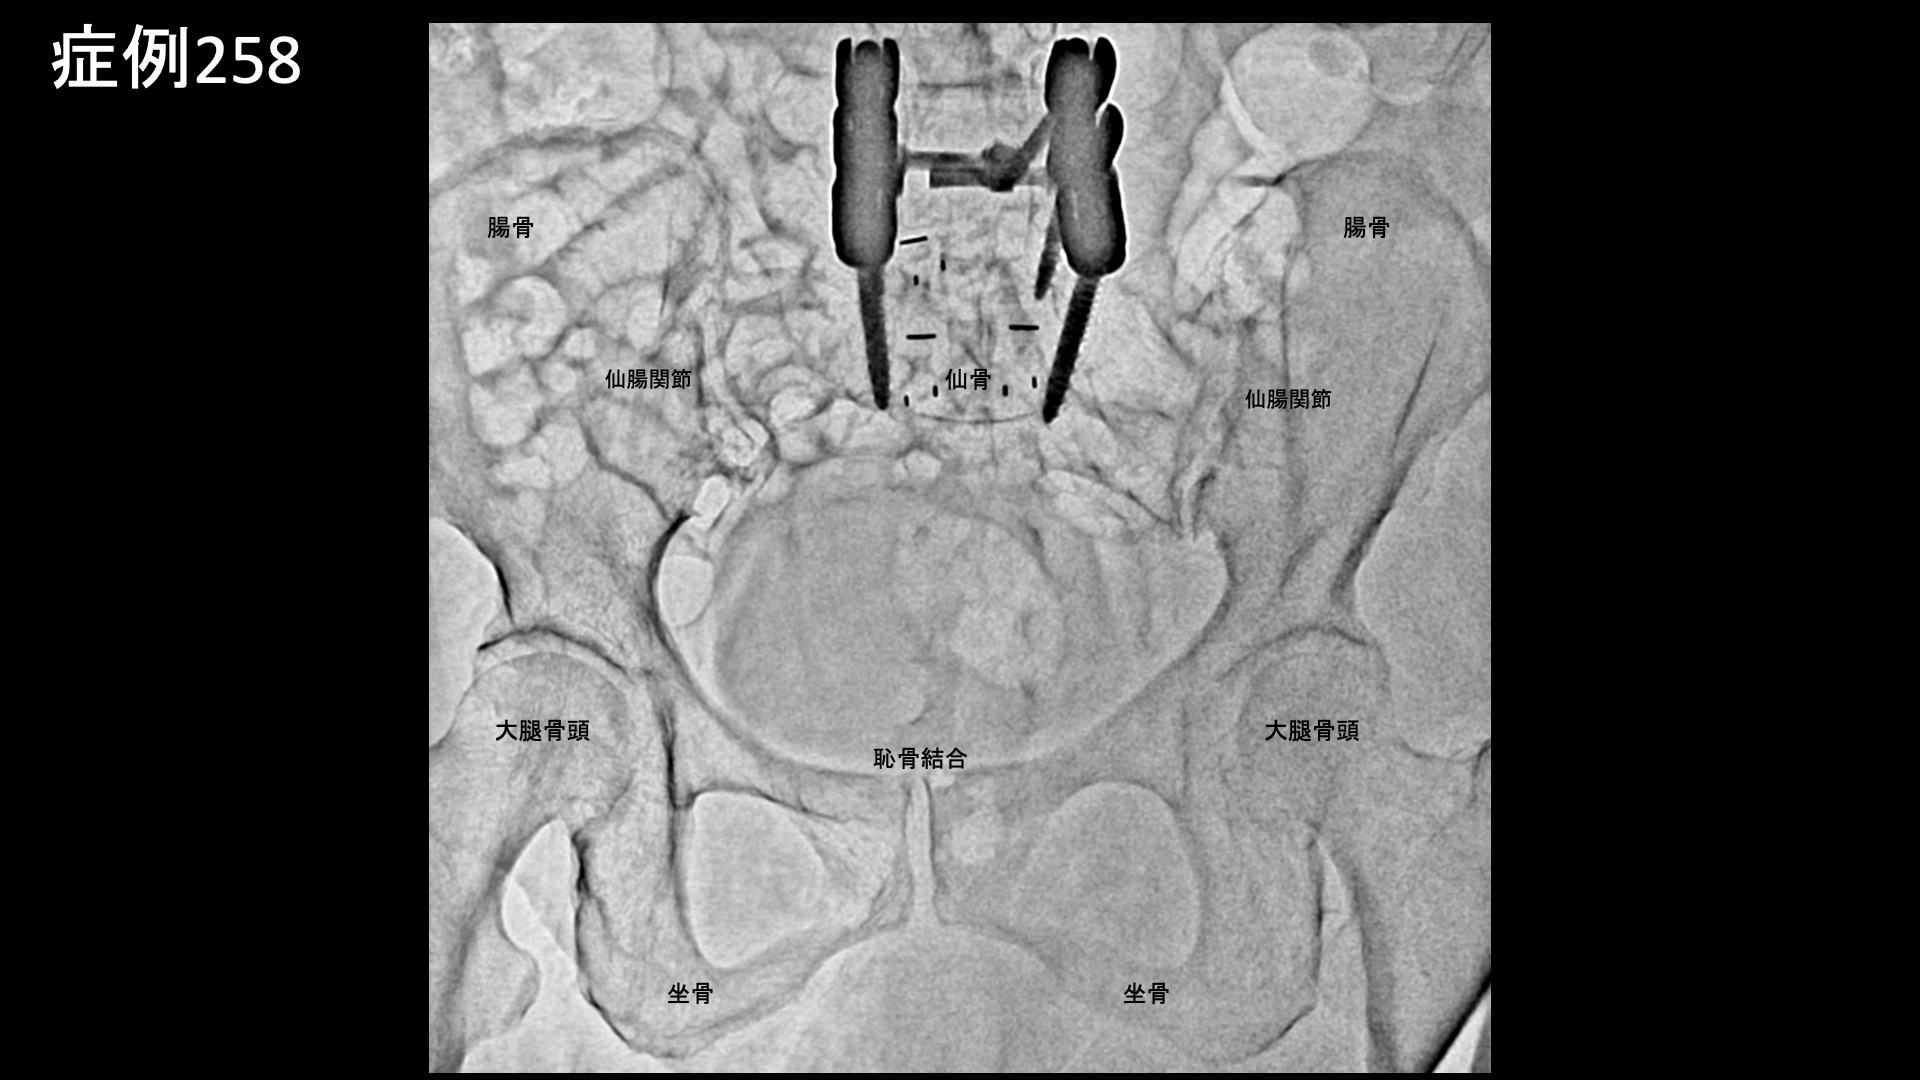

腰の可動域をチェックすると、前屈以外は全て高度に制限されていました。股関節の内外旋は可能でしたが、外旋時に鼠径部痛が誘発されました。L3/4,L4/5椎間関節、棘間靭帯に圧痛を認めました。さらに、上後腸骨棘(PSIS)、梨状筋、鼠径部、大腿外側に強い圧痛を認めました。レントゲンでは腰椎固定術後の様子を確認したほか、仙腸関節の骨硬化像、軽度の股関節変形を認めました。以上より総合的に判断し、仙腸関節障害、両側変形性股関節症、筋・筋膜性疼痛症候群、腰椎性腰痛(椎間関節炎、棘間靭帯炎)および両側坐骨神経障害(腰椎固定術後、脊柱管狭窄)の合併状態と診断しました。重症、高齢であり、複数回の治療を要する可能性があること、一定の症状は残存すること(特にしびれなどの感覚障害)などを十分ご理解いただいたうえでモヤモヤ血管(病的新生血管)に対する運動器カテーテル治療(微細動脈塞栓術)を受けていただきました。